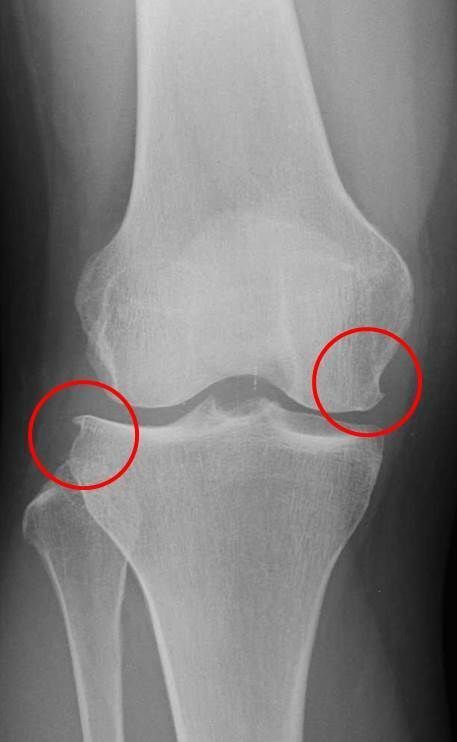

画像所見

| レントゲン | MRI | |

| 骨傷なし、骨棘あり Kellgren-Lawrence分類gradeⅡ | 外側半月板のフラップ損傷あり 骨損傷あり | |